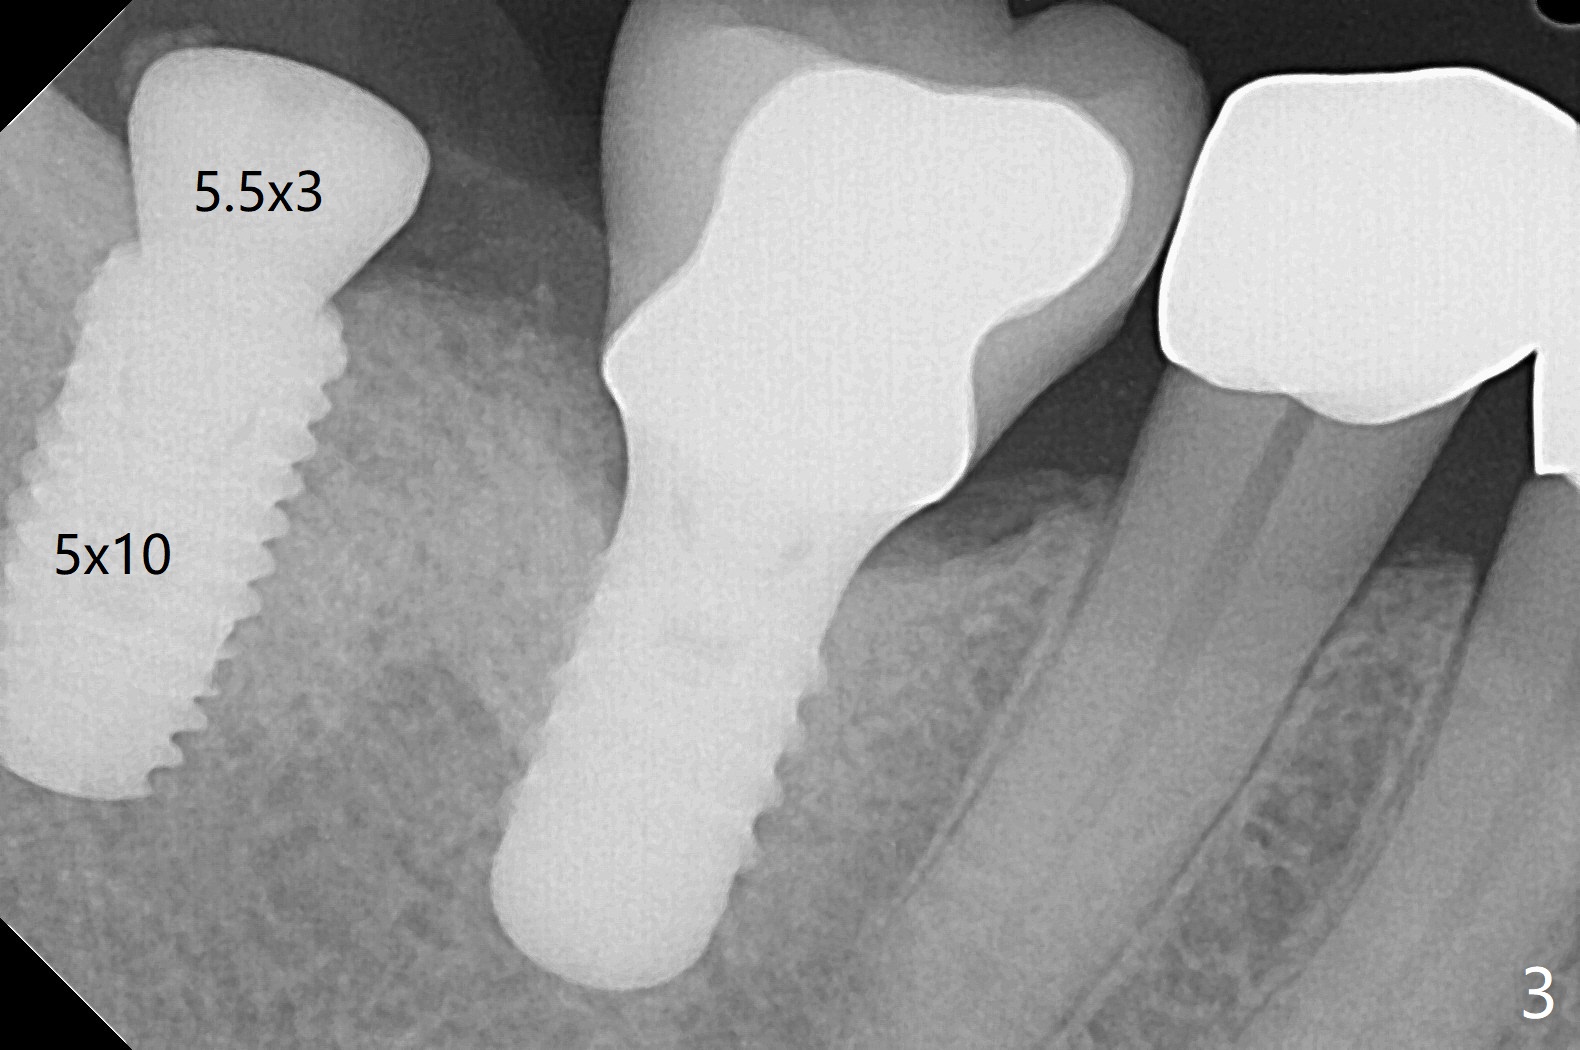

61岁女右下7导板钻洞,第一个钻头(环形钻)就有困难入位,部分磨去对合7近中腭侧牙尖(图一:*),钻头入位就好多了(图二:^,对比)。钻洞时发现骨质密度中等,所以最后钻头直径4.5毫米。不过无法用手植牙工具旋入植体,使用5.0毫米功螺纹钻头后,手工具就好用了,植体植入一定深度,扳手有空间插入,最后扭力30Ncm。第二个问题,当按照设计深度植入植体,用探针检查颊侧好像没有骨壁;加深大约0.5毫米(仿佛没有取到目的,颊侧骨板不明显)后,使用6毫米profile钻头,插入5.5x3毫米愈合基台(图二,三),在基台和颊侧牙龈之间植入异体骨粉,但愿帮助颊侧骨板再生。术后一周内敷料脱落,颊侧伤口愈合,好像骨粉没有流失。术后2.5月愈合基台脱落,换至小号基台(4向毫米),仍旧疼痛,休息2分钟,手拧紧,拍摄根尖片,仿佛就位(图四)。准备一周后调换稍微大,例如,4.8毫米基台。术后3.5个月,5.2毫米基台好像没有就位(图五:<),可能与远中牙槽嵴接触(*)。小一号基台仿佛就位(图六),与远中牙槽嵴无接触。术后4个月粘固后基台螺丝拧紧30Ncm。术后8个月,也就是粘固后4个月,牙槽嵴似乎试图覆盖植体平台(图七:箭头)。